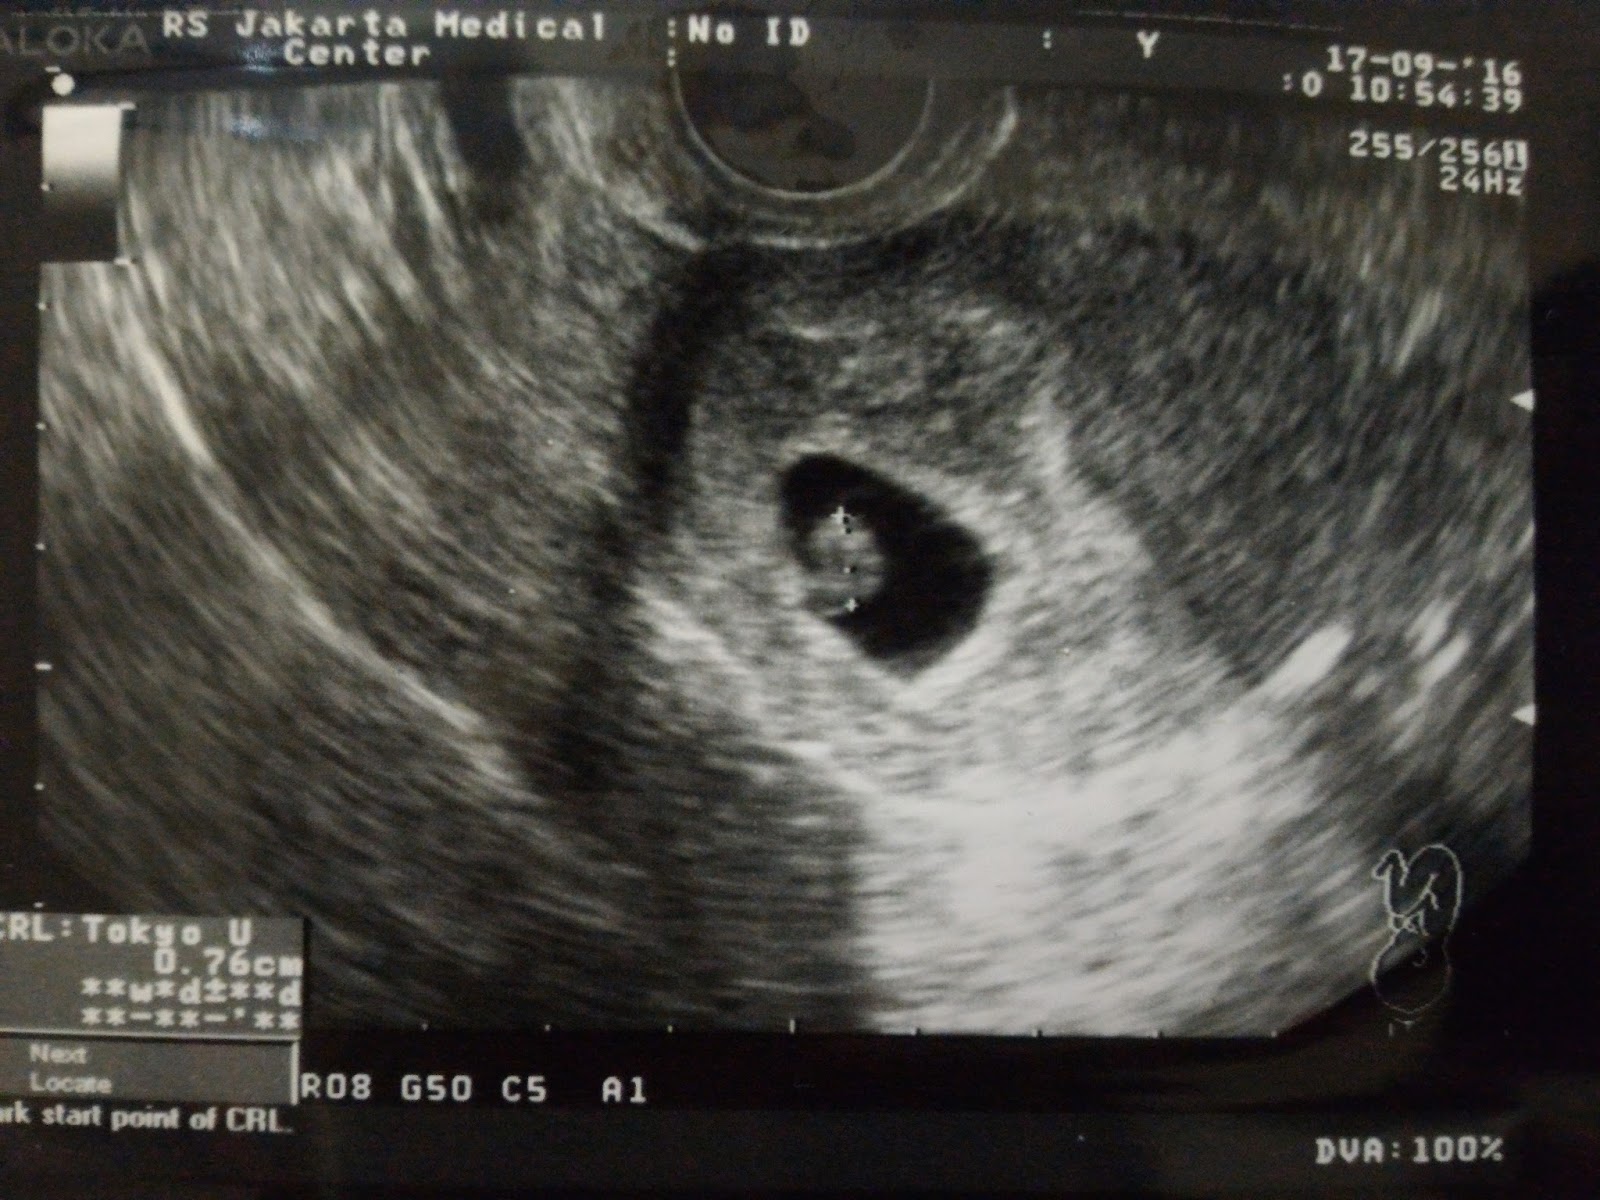

45+ Gambar Perut Hamil 6 Minggu. Pada video kali ini membahsa istilarh2 dan cara. Bentuk perut ibu hamil kembar ukurannya lebih besar daripada biasanya.